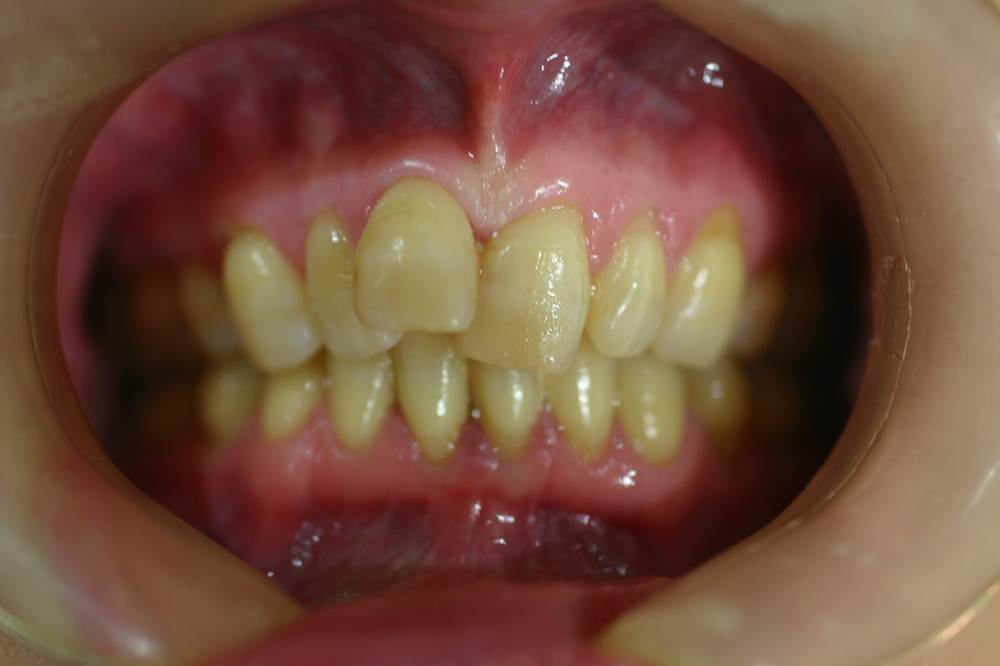

上顎が舌側矯正、下顎が唇側矯正の治療症例

Before

After

年齢 20代

治療期間 2年

治療費用 1,100,000円

治療のリスク 特になし